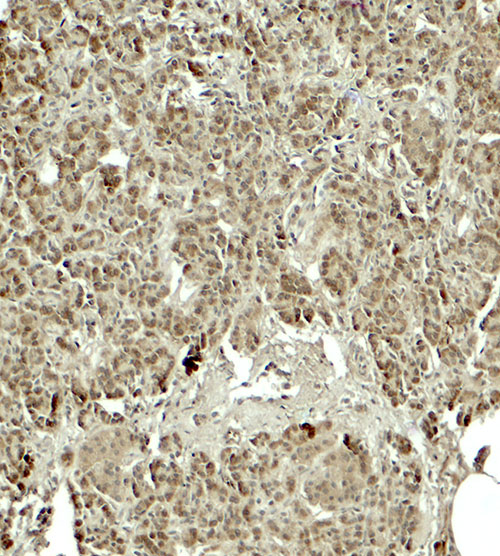

Immunohistochemistry of KIRREL2 in human pancreas tissue with KIRREL2 antibody at 5 μg/ml.